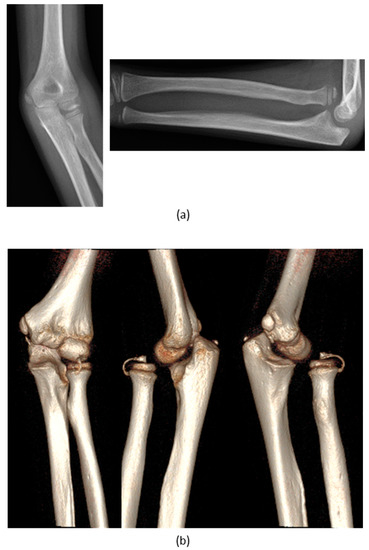

| 1 | F, 9 | Missed Monteggia Lesion | Post-traumatic | Proximal ulnar osteotomy stabilized with a 6-holes plate | None | Corrected |

| 2 | M, 13 | Focal fibrocartilagineous dysplasia | Congenital | Bifocal osteotomy stabilized with external fixator | Heterotopic bone formations | Fair (residual dislocation of the radial head with shortening of the ulna) |